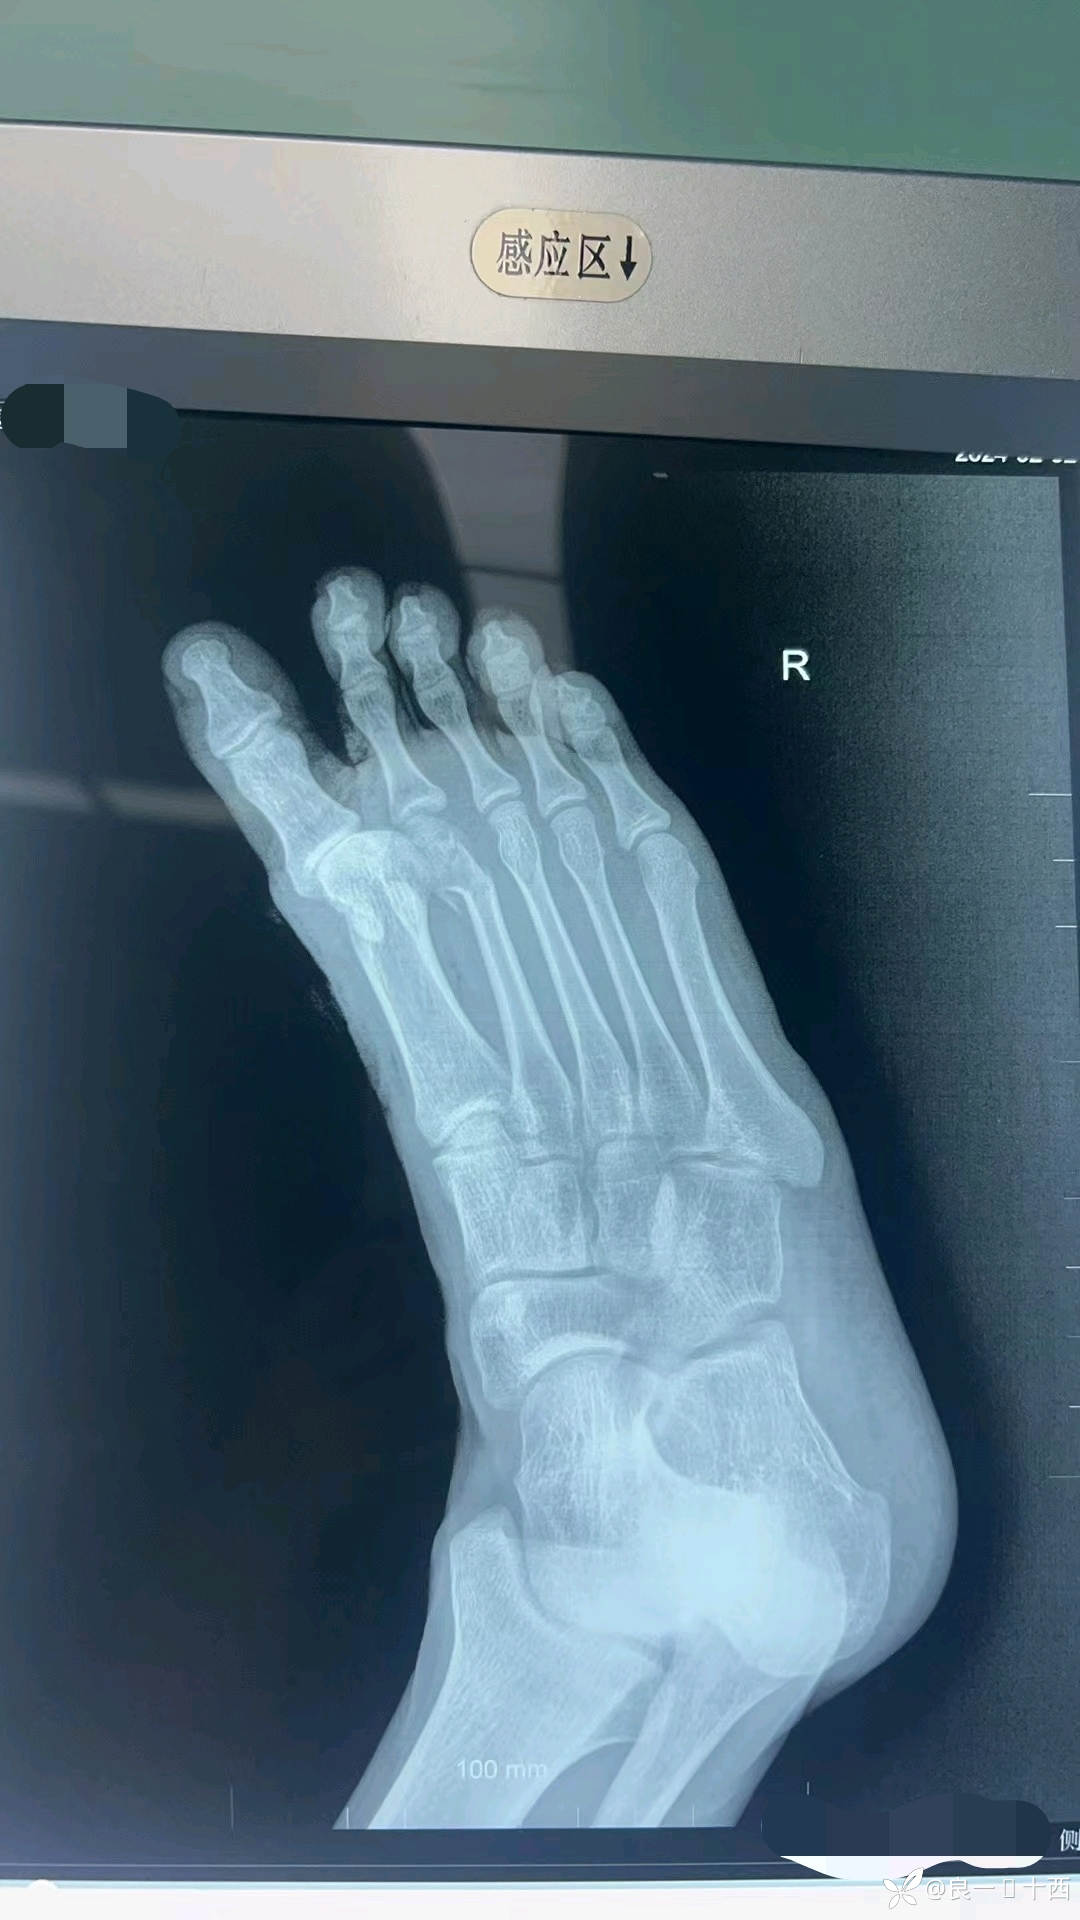

一位18岁帅气少年,应该是晚上通宵上网了,回来时候精神状态不佳,导致自己骑车出了车祸。初步检查后,得出诊断如下,右足拇趾基底部开放性撕脱骨折,拇收肌横头撕脱,第一跖趾关节开放性脱位,第二跖骨头开放性骨折,右足背内侧撕脱伤